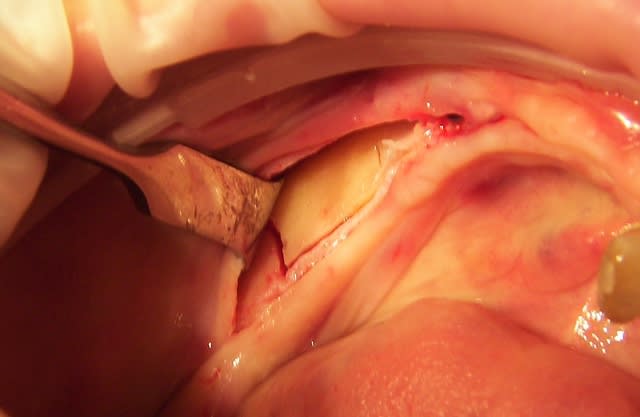

ce que je considère comme pas simple du tout expansion symphise.

ce fut long (pas loin de trois heures) mais bon!

3 h car je laisse l'os travailler , il faut qu'il "s'ecarte" lentement sinon craque.

pas du D1, sans fenetre laterale ça ne marcherais pas, par contre fin.